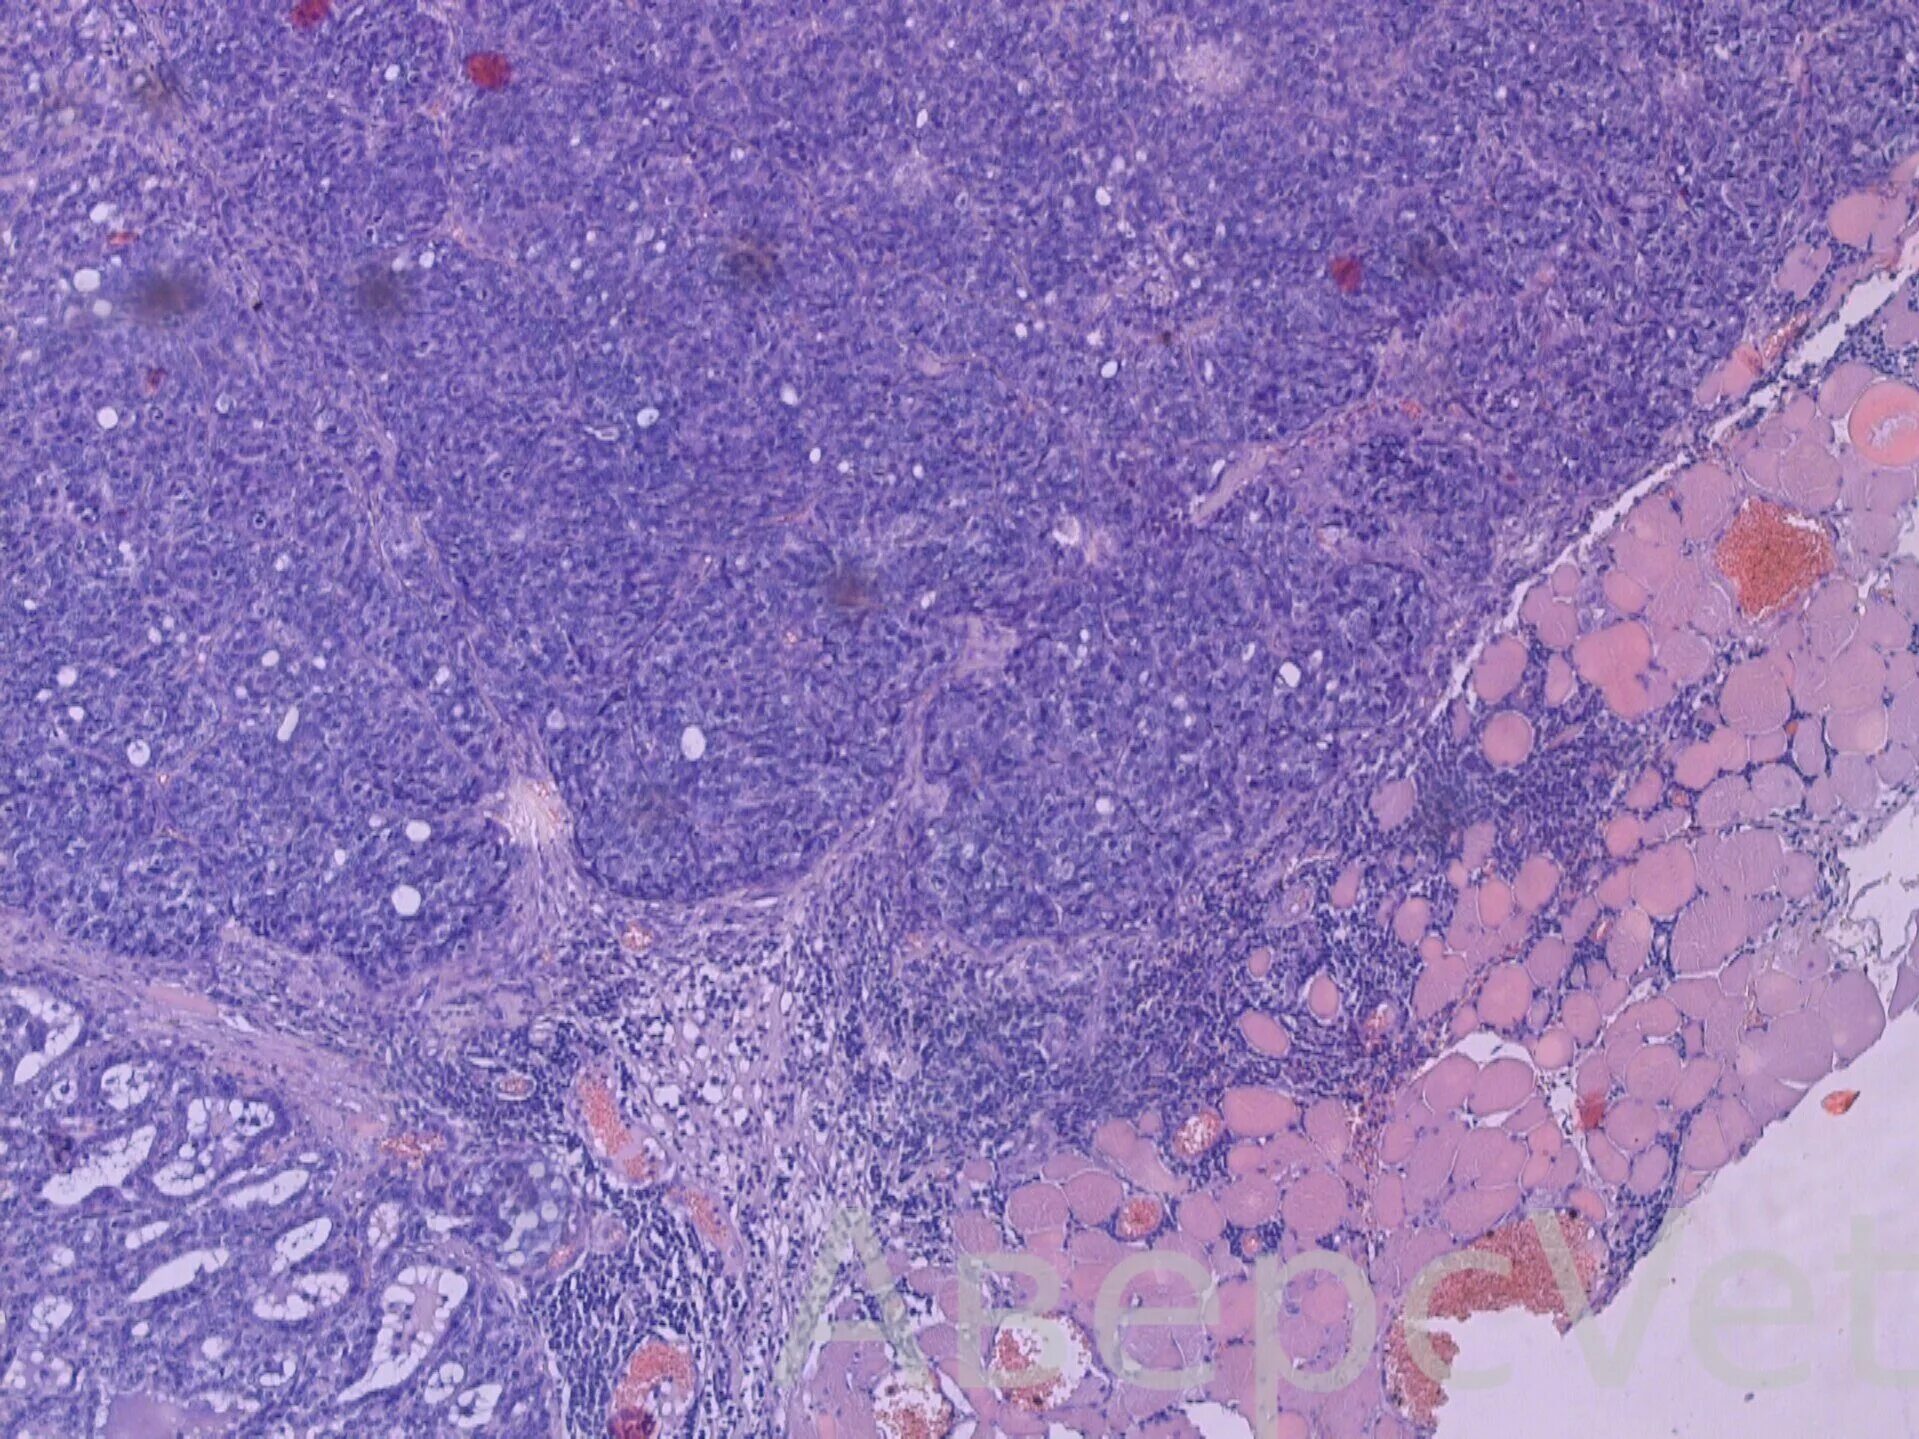

Гистохимия это